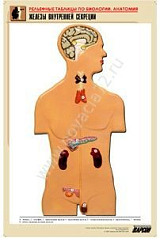

Комплект включает в себя 21 таблицу следующего содержания:

1. Железы внутренней секреции;